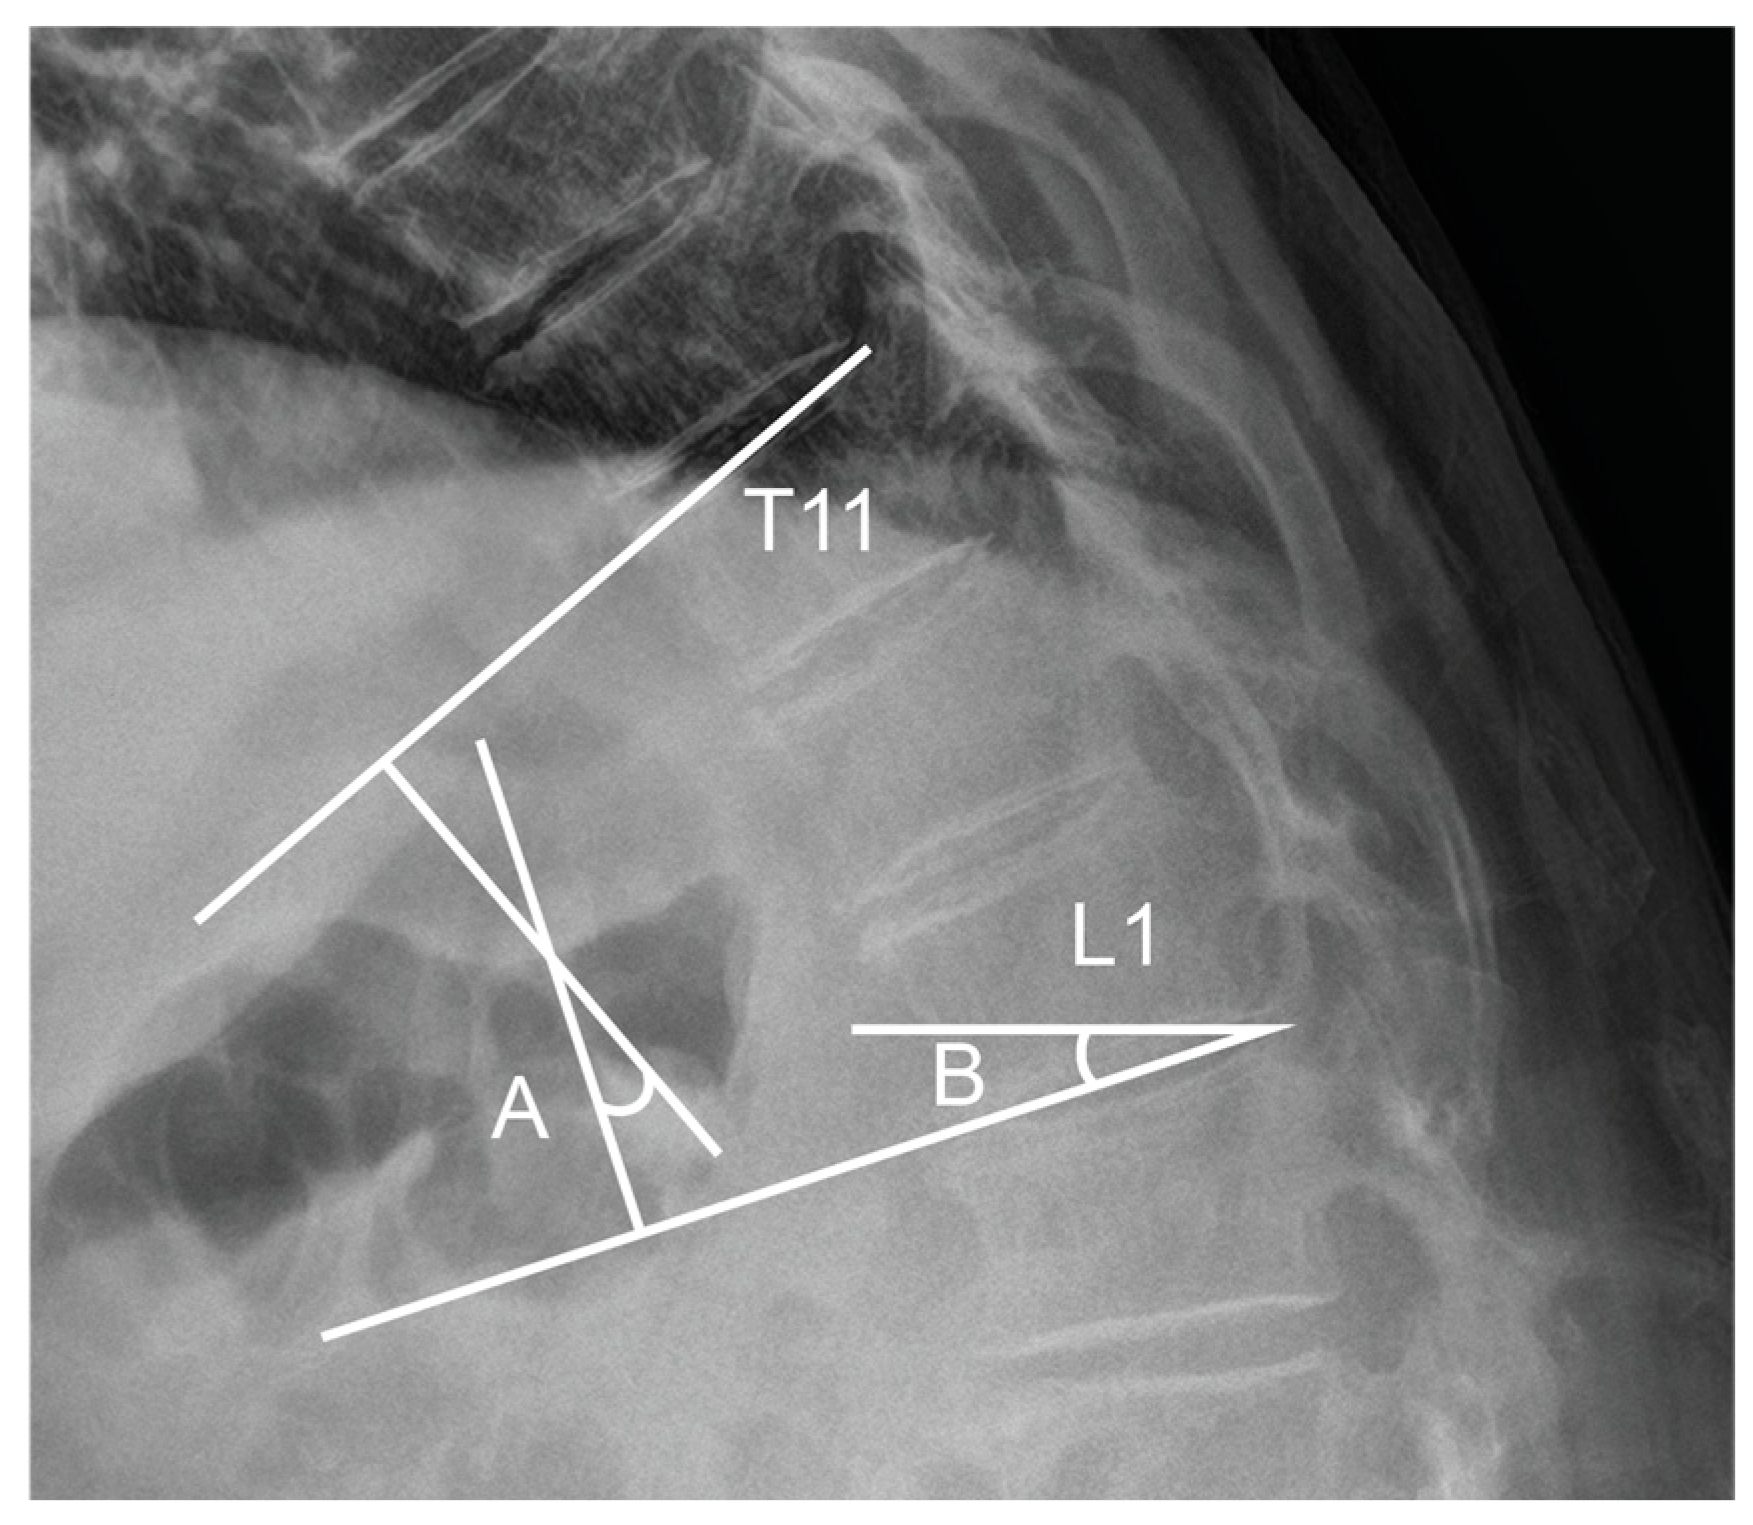

- Preoperative planning: The TLA and TLS were measured on standing lateral radiographs to define each patient’s baseline physiological curvature at the thoracolumbar junction. These values served as intraoperative references for targeted alignment.

- Controlled distraction: Distraction was sequentially applied between UIV–UIV-1 and UIV-1–UIV-2 using a rod distractor or compressor system. Under radiographic guidance, distraction was adjusted with the goal of producing a segmental kyphosis 5° to 10° greater than the angle measured between UIV and UIV-2 in the prone position. Set screws were progressively tightened during this process to maintain the desired curvature and ensure gradual stress distribution.

- Moon, H.J.; Bridwell, K.H.; Theologis, A.A.; Kelly, M.P.; Lertudomphonwanit, T.; Lenke, L.G.; Gupta, M.C. Thoracolumbar junction orientation: A novel guide for sagittal correction and proximal junctional kyphosis prediction in adult spinal deformity patients. Neurosurgery 2021, 88, 55–62. [Google Scholar] [CrossRef]

- Ham, D.-W.; Kim, H.-J.; Park, S.-M.; Park, S.J.; Park, J.; Yeom, J.S. The importance of thoracolumbar junctional orientation, change in thoracolumbar angle, and overcorrection of lumbar lordosis in development of proximal junctional kyphosis in adult spinal deformity surgery. J. Neurosurg. Spine 2022, 37, 874–882. [Google Scholar] [CrossRef]